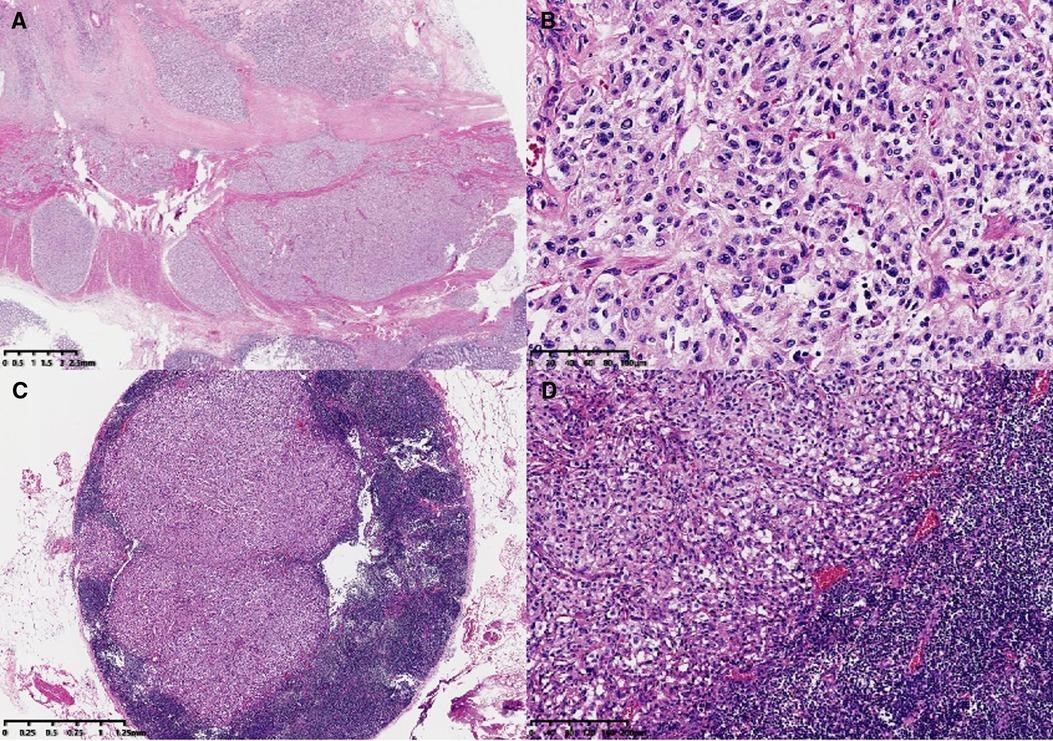

肿瘤主体位于肠壁肌层和浆膜下层,侵犯局部浆膜和黏膜固有层。形态学上,肿瘤类似于巢状和器官状结构。肿瘤细胞胞浆丰富,核异型性明显,核分裂象<1/10高倍视野。观察到轻度淋巴血管侵犯和神经侵犯。部分肿瘤细胞轻度变性伴间质性玻璃样变,与治疗后轻度反应一致。此外,还可以看到淋巴结(18/33)和肿瘤结节中的转移性肿瘤(图1 ))。由于在患者的影像学检查和手术过程中没有发现其他肿瘤,因此首先考虑了结肠的原发性肿瘤。免疫组化染色结果(图2):AE1/AE3、CK18、EMA等上皮标志物均为阴性,提示可排除低分化腺癌和神经内分泌肿瘤的诊断。CD56、Chromagranin-A、突触素、SSTR2和NSE等神经内分泌标志物呈弥漫性强阳性表达,支持副神经节瘤的诊断。S-100、SOX10 和 GFAP 的免疫染色突出显示了支持细胞,可以在 Zellballen 的外围发现不同数量的支持细胞或散布在肿瘤细胞之间。HMB-45阴性,MelanA呈弥漫性中度表达,不能排除透明细胞肉瘤的诊断,需要分子检测进一步诊断。此外,Desmin、SMA、CD117、TTF-1均为阴性。Vimentin呈弥漫性强细胞质阳性。GATA3呈弥漫性核阳性,抑制素呈局灶性阳性,CD34呈血管阳性。Ki-67 标签指数约为 5%。SDHB呈弥漫性阴性,代表突变表达。

图 1。微观特征。肿瘤主体位于结肠壁肌层和浆膜下层(A,×6)。高倍镜下,肿瘤形态呈巢状、器官样结构(Zellballen型)(B,×200)。淋巴结转移(C,×20;D,×100)。